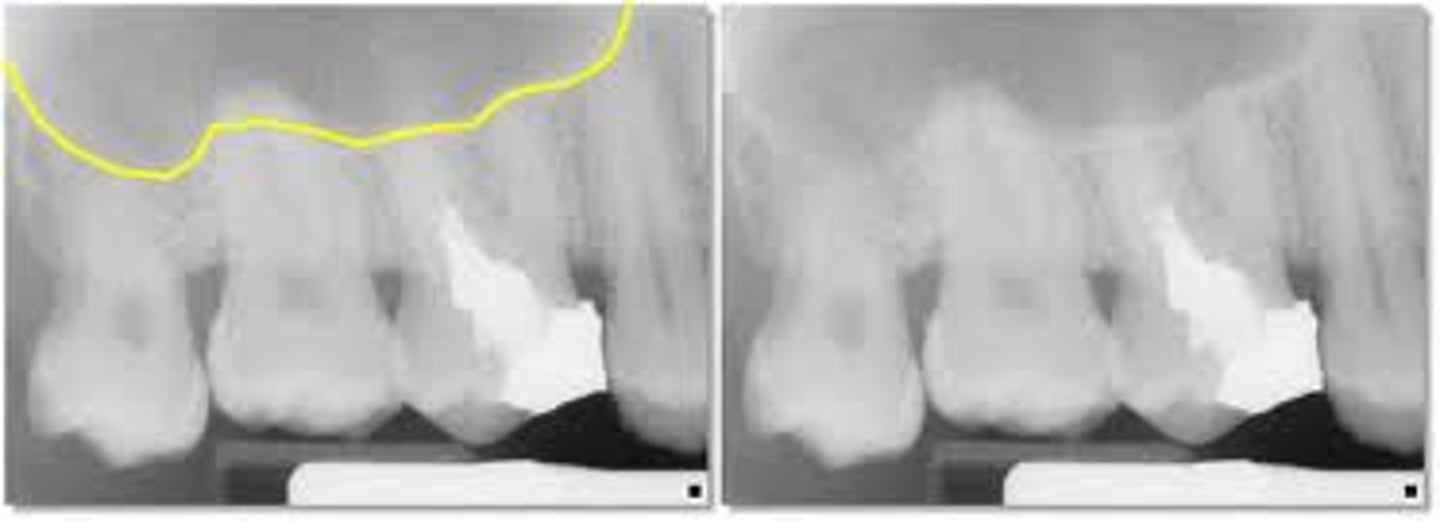

lower border of the sinuses

radiopaque

floor of the sinus

submandibular gland fossa

rounded area of bone

less dense

space for submandibular salivary gland